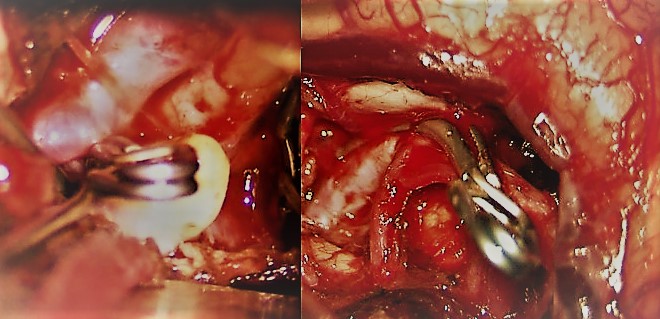

Tratamiento microquirúrgico de tumores cerebrales

Con una metodología de trabajo definida por nuestro firme compromiso con:

1. Seguridad del paciente

2. Planificación quirúrgica

3. Excelencia en la técnica microquirúrgica

4. Compromiso con el conocimiento científico